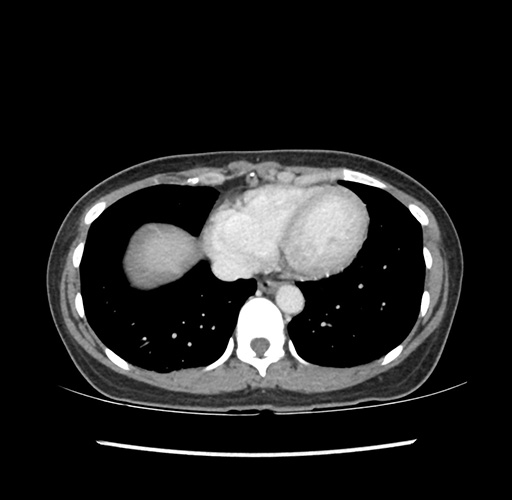

Imaging Analysis

Look through the patient's CT scan to identify any areas of concern for the necessary procedure.

Based on your CT findings, which issue(s) would give reason for "planned slowing down moment(s)" in this case?